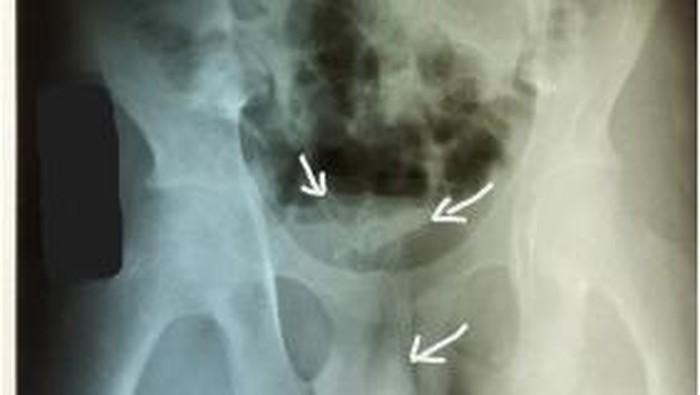

Para dokter di rumah sakit di Kolombo, Sri Lanka, menemukan massa melingkar yang tidak diketahui di perut pasien melalui pemindaian ultrasonografi.

Mereka melakukan prosedur cepat yang disebut sistoskopi, dengan memasukkan tabung berlampu dan kamera di ujungnya ke dalam uretra. Ini berfungsi untuk melihat ke dalam kandung kemih.

Setelah mereka mendapat gambaran yang lebih komprehensif tentang kabel di kandung kemih remaja itu, dokter baru bisa mengangkatnya melalui pembedahan.